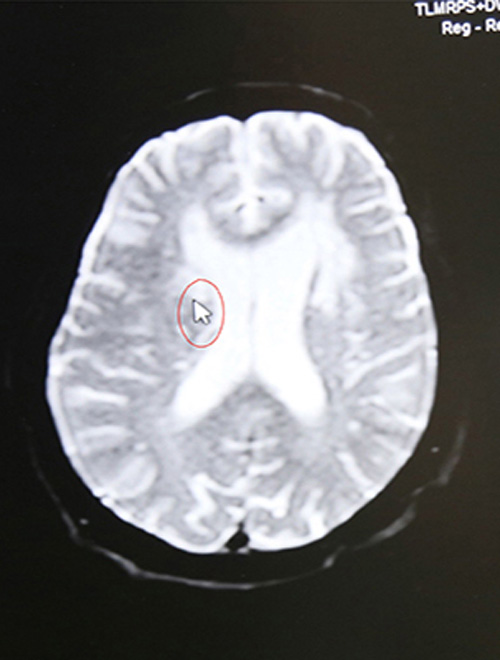

颅脑MRI示:右侧基底节区脑梗塞

16:44 影像科3分钟出报告,CT报告显示:排除脑出血。为进一步查看脑血管情况,又迅速完成了颅脑血管磁共振检查,结果显示:脑梗塞。

(结合影像学检查,了解到老人有脑梗发病史,李振并主任判断患者系急性脑梗,发病时间为15:30,还处于静脉溶栓治疗3小时的时间窗内,有溶栓治疗指征,可溶栓治疗,积极治疗血管有再通希望。)